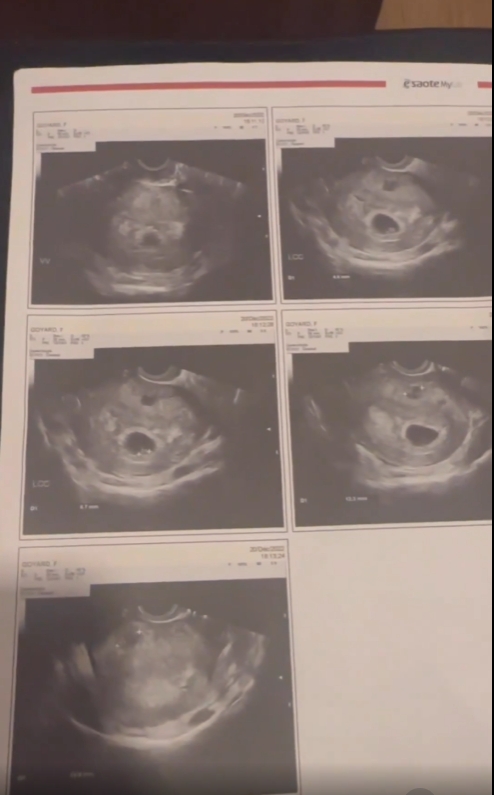

“ลาล่า อาร์สยาม” โชว์ผลอัลตาร์ซาวน์ ประกาศข่าวดี “น้องสาว” ท้องลูกคนที่สองแล้ว

ทำเอาคนในครอบครัวดีใจกันสุดๆ จนน้ำตาไหลกันเลยทีดียว สำหรับ “ลาล่า ขวัญนภา เรืองศรี” หรือ “ลาล่า อาร์สยาม” หลังเจ้าตัวได้โพสต์คลิปโชว์ภาพผลอัลตร้าซาวด์ พร้อมประกาศข่าวดี น้องสาวของเธอที่แต่งงานกับสามีชาวฝรั่งเศส ได้ตั้งท้องลูกคนที่สองแล้ว โดยระบุข้อความว่า..

“ท้องแล้ว..เย้ๆๆ รอมานาน ฝรั่งเศสน้อยมาแล้ว หลานคนที่ 2 ดีใจที่สุดในชีวิต ชาตินี้ก็คุ้มค่าที่สุดแล้ว น้ำตาแห่งความสุข ขอต้อนรับสมาชิกตัวน้อยอีกคนนะลูก ขอให้หนูแข็งแรง อีก 5 เดือนเจอกันนะลูก เย้ๆๆๆ”